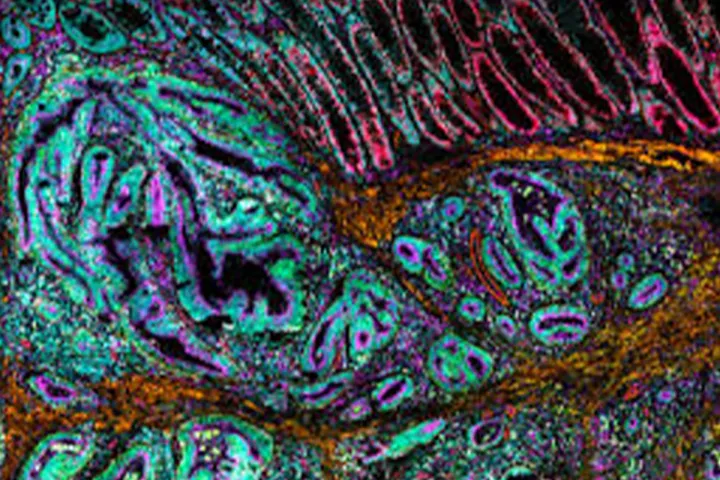

The MACSima platform offers fully automated ultra-high-content imaging based on cyclic immunofluorescence, enabling researchers to analyze hundreds of markers within a single tissue section or cell sample without damaging the specimen. This approach provides precise spatial insight into cell localization and interactions within complex tissue environments.

The system breaks the conventional limits of fluorescence multiplexing and is particularly suited for deep phenotyping applications, including immuno-oncology (tumor microenvironment mapping), neuroscience, and the study of complex infectious diseases.